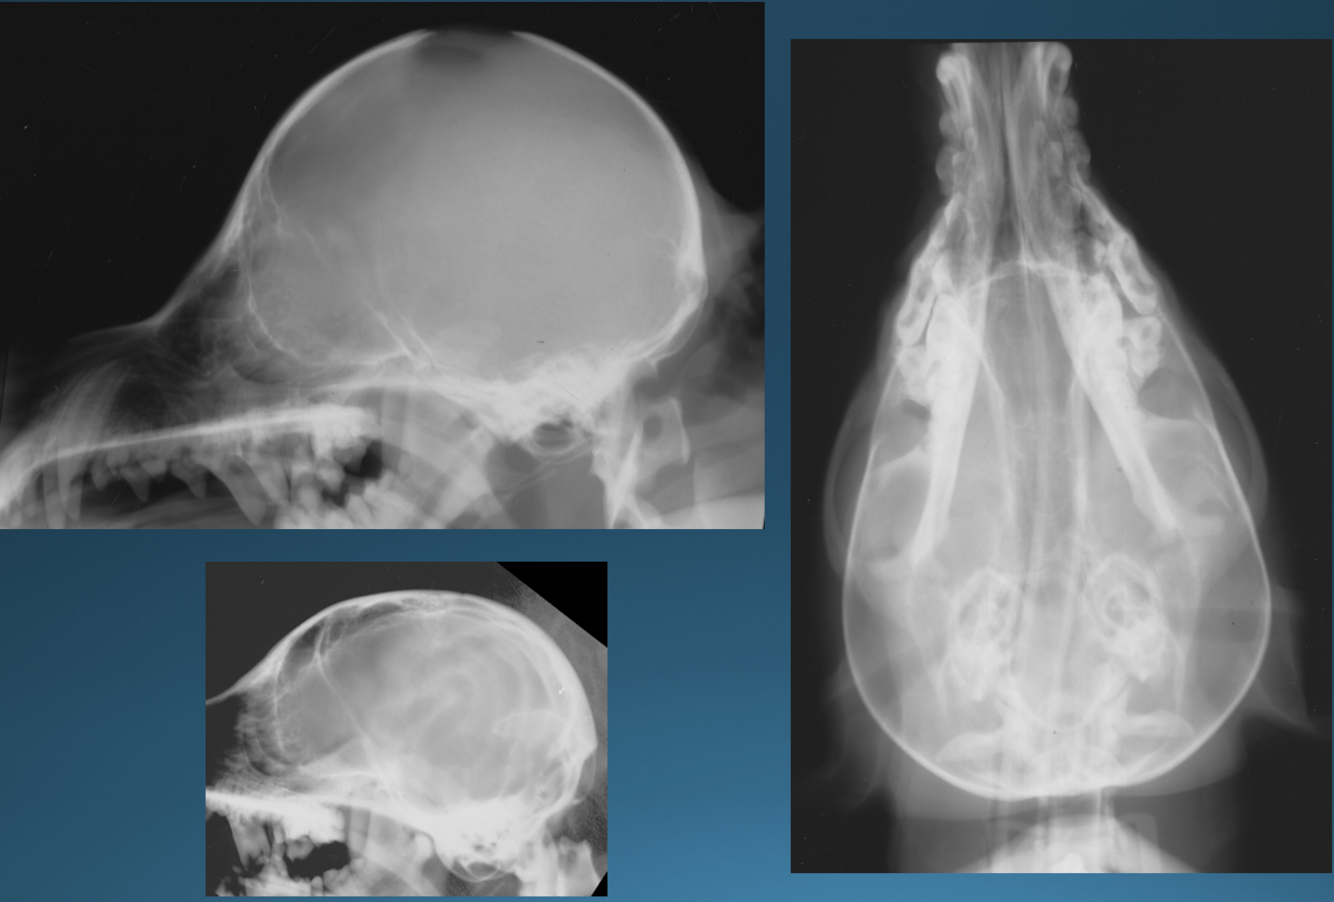

Q

What is shown in these images?

A

thinning of calvarium due to hydrocephalus